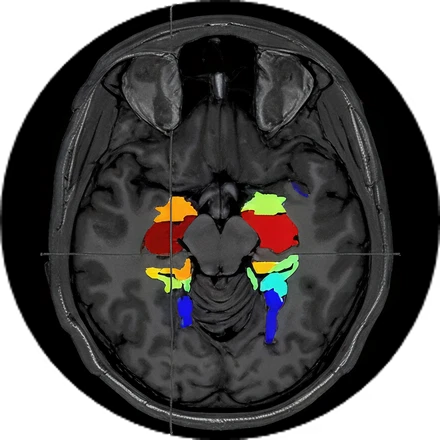

fMRI

Functional (fMRI)

3.0T

0.5T

Images from: Halder et al., Investigating the feasibility of resting state functional MRI with GRE EPI on a high performance 0.5 T Scanner, processed using GraphICA, an asset of Brainet-Brain Imaging Solutions Inc.